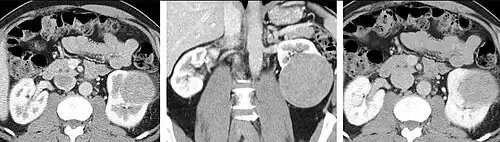

Detection and characterization of renal parenchymal masses is a frequent indication for CT. An initial noncontrast CT is important for detecting calcium or fat in a lesion, and to provide baseline attenuation of any renal masses. Following noncontrast scanning, intravenous contrast is injected and a corticomedullary phase is obtained at approximately 70 seconds (figure 7a, 7b). The corticomedullary phase is characterized by enhancement of the renal cortex as well as the renal vasculature. This phase is valuable in the evaluation of benign renal variants, lymphadenopathy and vasculature, however certain medullary renal masses may not be visible during this phase due to minimal enhancement of the medulla and collecting system. The parenchymal phase is obtained approximately 100–200 seconds after the injection of contrast material (figure 7c). Parenchymal phase imaging demonstrates continued enhancement of the cortex, enhancement of the medulla, and various levels of contrast material in the collecting system. The parenchymal phase is highly important for the detection and characterization of renal masses, parenchymal abnormalities, and the renal collecting system. This method of imaging does not evaluate for abnormalities of the collecting system.

- FIGURE 7. Selected images from a renal mass specific protocol CT. Corticomedullary phase (axial 7a) demonstrates peripheral enhancement of the renal cortex with minimal opacification of the renal medulla. There is a large renal cell carcinoma in the left kidney (right in image) which can be differentiated from the normal renal parenchyma by the heterogeneous and differential enhancement. The renal artery and vein are opacified in this phase as well. The collecting system is not opacified (coronal reformat 7b). In the parenchymal phase, the renal cortex and the medulla are enhancing. The renal cell carcinoma in the left kidney is not as well defined when compared to the corticomedullary phase images, but is actually slightly more conspicuous. There is some contrast noted within the collecting system during this phase (7c).